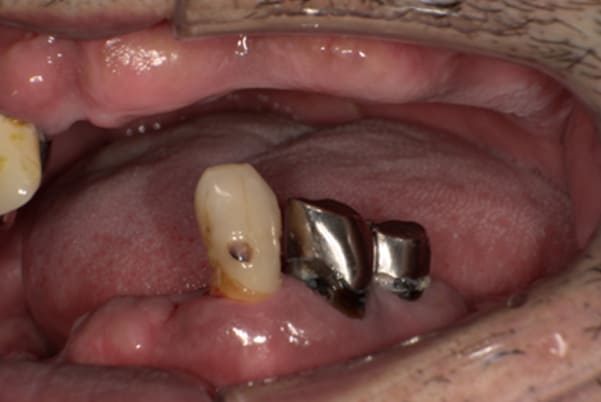

症例レポート[CASE.06]

- 男性(70代)

- 下歯がぐらぐらで抜けそうで痛い、何でも咬めるようにしてほしい

- 治療

- 上顎精密金属床部分入れ歯

- 下顎精密金属床部分入れ歯

- 陶材焼付鋳造冠 4歯

- 磁性アタッチメント 1歯

- 治療期間

- 約6か月間

- 費用

- 上顎精密金属部分入れ歯:55万円

- 下顎精密金属部分入れ歯:77万円

(治療用義歯含、咬合平面等修正) - 陶材焼付鋳造冠:16.5万円×3歯

(ミリング加工) - 陶材焼付鋳造冠:14.3万円×1歯

(ミリングなし) - 磁性アタッチメント:11万円×1歯

(白金加金)

合計:157.3万円(税込)

奥歯がなくなり放置されていたため、前歯に負担がかかり、歯周病も併発されており歯がぐらぐらでお痛みも伴う状態でした。

可能な限り残せる歯は保存し虫歯治療を行い、どうしても残せないお痛みの歯のみ抜歯を行いました。

陶材焼着付鋳造冠 ミリングラべット加工

残りの歯が少ない場合は、入れ歯が動きやすく、またご自身の歯にも負担がかかるため、残りの歯の被せ物、入れ歯ともに、歯に負担がかかることを最小限にした特殊な加工を行い、歯を長持ちさせる設計としました。